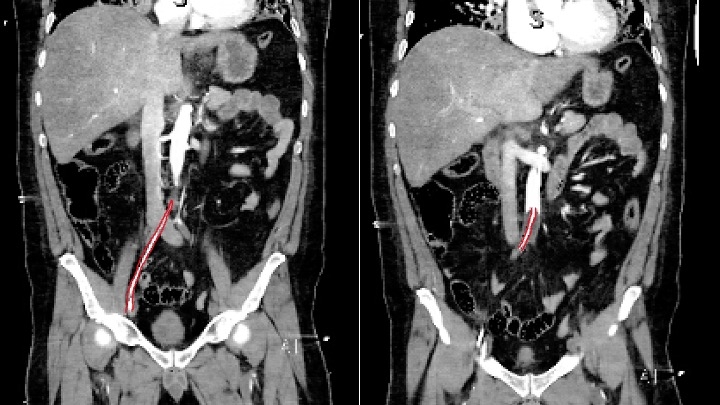

Successful Deployment of Resuscitative Endovascular Balloon Occlusion of the Aorta by Emergency Medicine Physicians for Refractory Non-Traumatic Out of Hospital Cardiac Arrest

Resuscitative endovascular balloon occlusion of the aorta (REBOA), initially developed to manage non-compressible torso hemorrhage, is a promising intervention for enhancing coronary and cerebral perfusion in non-traumatic cardiac arrest. This procedure can increase rate of return of spontaneous circulation (ROSC) or serve as a bridge to extracorporeal cardiopulmonary resuscitation (ECPR).

Eight patients, 5 males and 3 females (age range 25-79), underwent REBOA placement. First pass success was 8/8 (100%) REBOA catheters from all 3 commercially available catheters in the United States were used. ROSC was achieved in 3/8 (37.5%) patients, although all patients died after hospital admission. No REBOA associated complications were identified on imaging or autopsy reports.

All REBOA placements performed by trained emergency physicians in patients with OHCA were successful after our training protocol, resulting in ROSC in 37.5% with no long term survivors. Based on the demonstrated success rate, we hope to further examine the feasibility and utility of REBOA in the pre-hospital setting for patients with refractory cardiac arrest as a bridge to earlier ROSC or additional ECPR therapies.